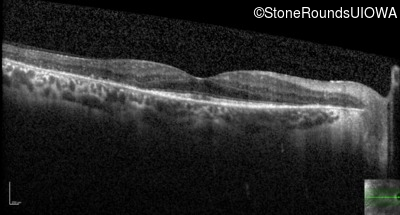

Age at visit: 60 years

Age at visit: 60 years (Visit 2)